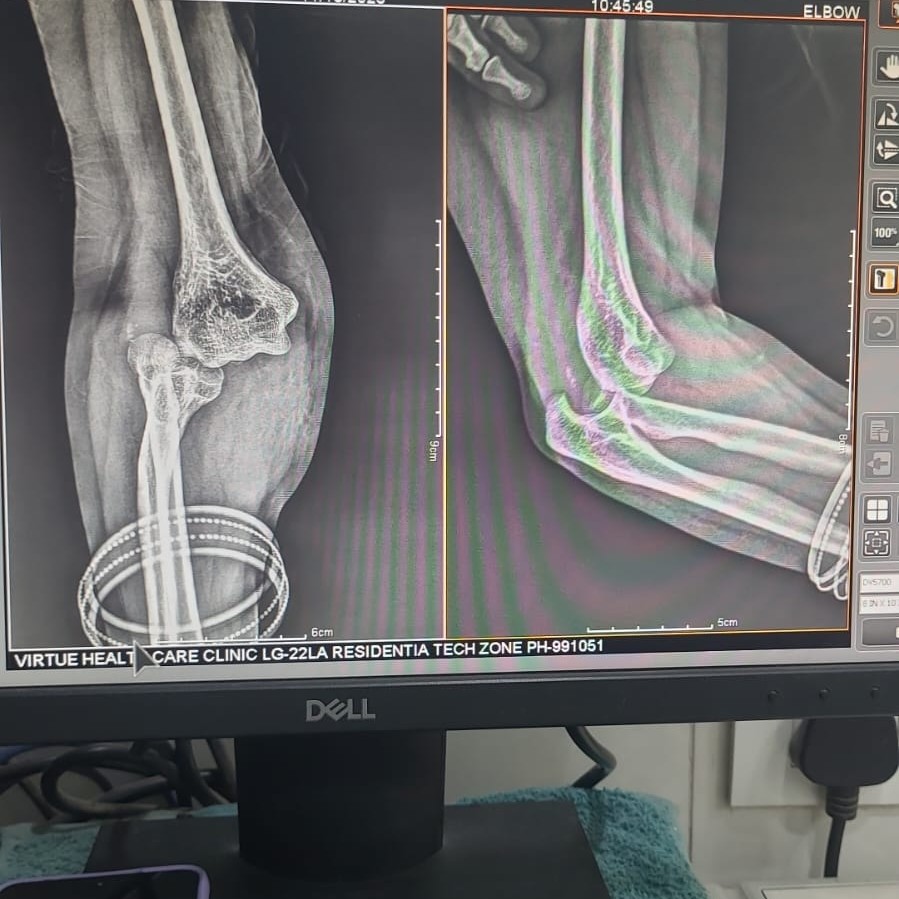

Dr Abhishek Kumar Orthopaedic Clinic LG 22 La Residentia Tech zone 4, Greater Noida west, Uttar Pradesh 201308 +918042753310 Hi.drabhishekkumar@gmail.com